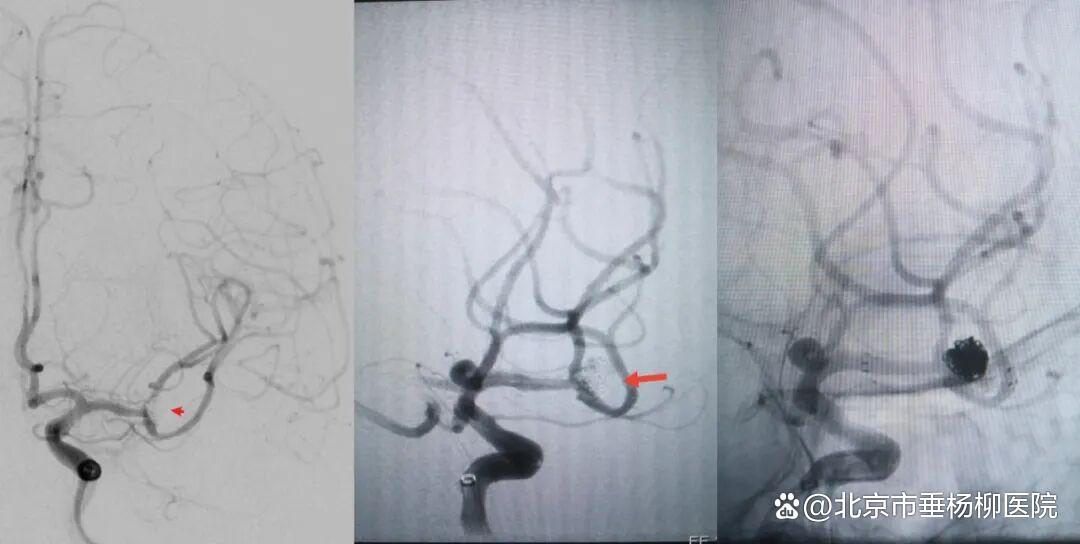

病例一为77岁女性患者,既往高血压病史。因“突发剧烈头痛伴恶心2天”前来清华大学附属垂杨柳医院急诊科就诊。头颅CT检查提示蛛网膜下腔出血,头颈动脉CTA提示右侧大脑中动脉M1段分叉处宽颈动脉瘤。神经外科脑血管病介入团队急诊为患者实施了全脑血管造影术(DSA),造影显示动脉瘤不规则,可见子囊,宽颈,主要累及下干。团队采取了支架辅助弹簧圈栓塞术,患者颅内“不定时炸弹”被成功拆除。动脉瘤达到致密栓塞,载瘤动脉通畅。住院半个月后顺利出院,无神经功能障碍。

▲术前DSA显示宽颈动脉瘤,有子囊,主要累及下干

▲术后DSA显示动脉瘤致密栓塞,载瘤动脉通畅